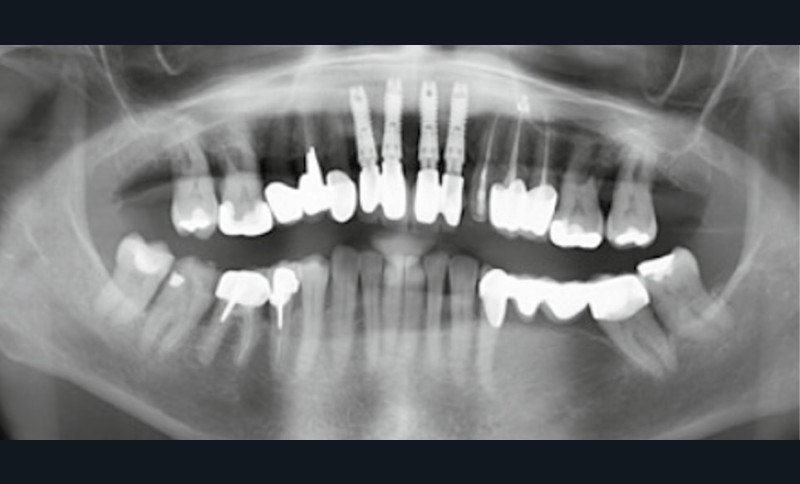

Une patiente ayant perdu ses incisives maxillaires à la suite d’un traumatisme quelques années auparavant, consulte en 2015 pour un inconfort occlusal persistant. Elle a été traitée par diverses gouttières occlusales, sans résultat notable. En 2017, une reconstruction globale est réalisée, toujours sans résolution de la plainte d’inconfort occlusal. Après avoir consulté de très nombreux praticiens et bénéficié de multiples traitements, en 2024 la patiente a perdu l’ensemble de ses dents ! En octobre 2025, après plusieurs prothèses globales sur implants, la plainte est toujours la même dans un contexte psycho-émotionnel de plus en plus difficile (fig. 1).